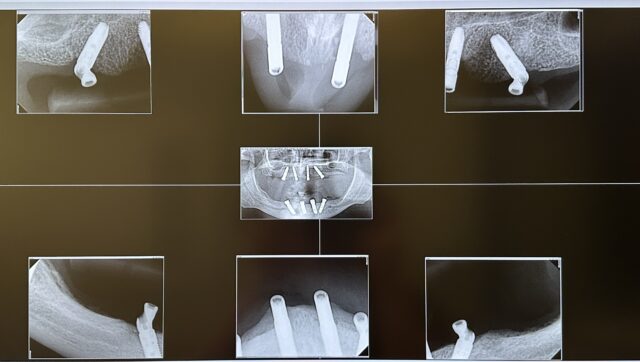

Update for those interested on the case I posted about not too long ago.

We went with custom milled locators from TruAbutment to angle correct. The case turned out really well!

Looking for some guidance on restoring this case.

The patient had these Astra EV implants placed by a periodontist. The plan with the then restorative dentist was CONUS attachments.

The patient left the restorative dentist and came to us. He no longer wants to do CONUS or a bar overdenture due to finances.